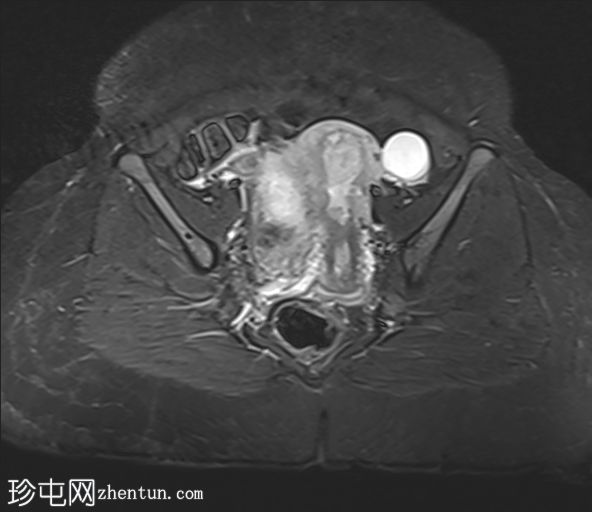

轴位

STIR序列

2.jpg

子宫体积增大,宫底可见息肉样病变,T2加权像呈异常中高信号强度。病变可见轻度扩散受限,增强后呈均匀强化。病变与宫底交界区之间可见一界限清晰的异常高T2信号区域,可能为囊性变性。未见病变超出交界区。

在剖宫产切口远端的前壁上,可见另一处类似的较小病灶。

左侧附件囊性病变,T1加权像信号异常低,T2加权像信号异常高。无增强扫描强化。

子宫内膜息肉是子宫内膜组织的结节状突起。通常表现为T2加权像信号异常高,增强扫描后呈均匀强化。

病理检查通常显示增生期子宫内膜紊乱。